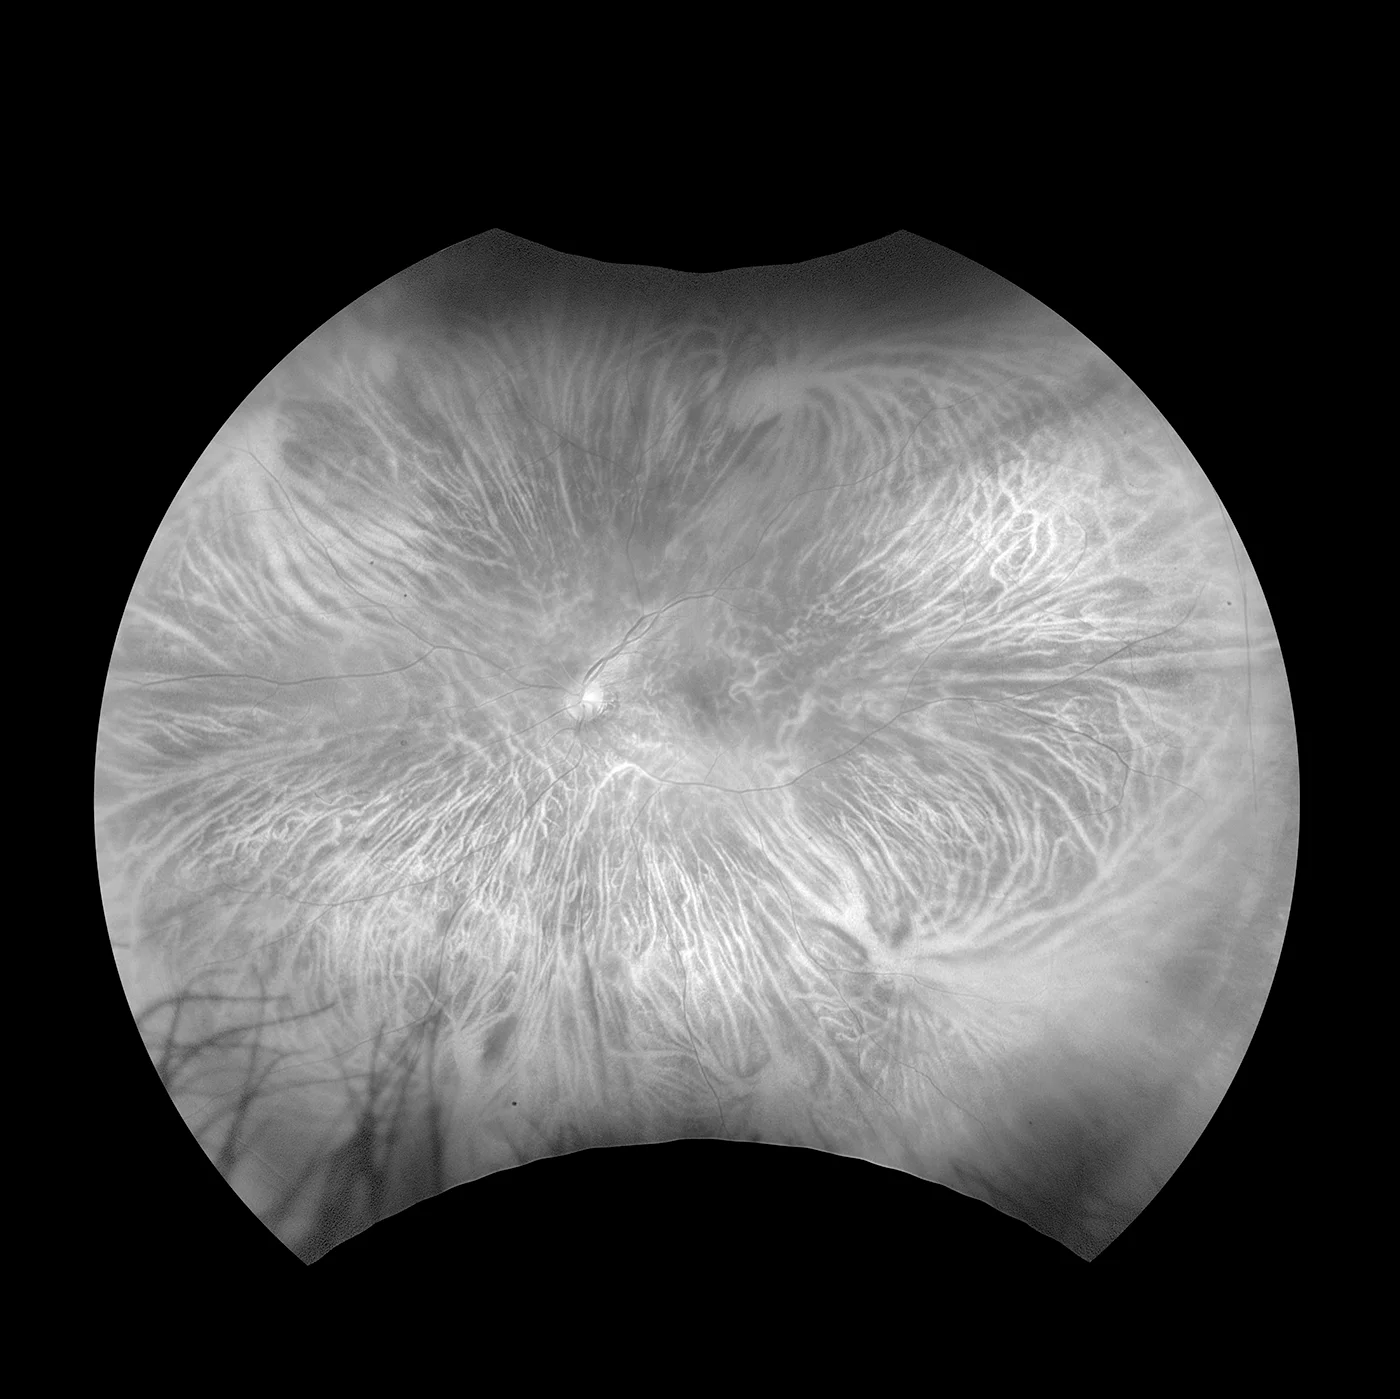

Silverstone ist das derzeit leistungsfähigste Gerät zur Untersuchung der Netzhaut. Als einziges Ultra-Weitwinkel-Bildgebungsgerät mit integriertem, geführtem Swept-Source-OCT liefert Ihnen Silverstone mit einer einzigen Aufnahme und in weniger als ½ Sekunde ein 200° optomap Bild der Netzhaut und ermöglicht zudem geführte OCT-Aufnahmen bis in die Peripherie der Netzhaut.

Bildgebungsmodalitäten und Darstellungsoptionen von Silverstone:

optomap Bildmodi

- Farbe rg

- Sensorisch Rotfrei

- Choroidal

- Autofluoreszenz

- Fluoreszenzangiographie

- Indocyaningrün-Angiographie

- Swept-Source OCT